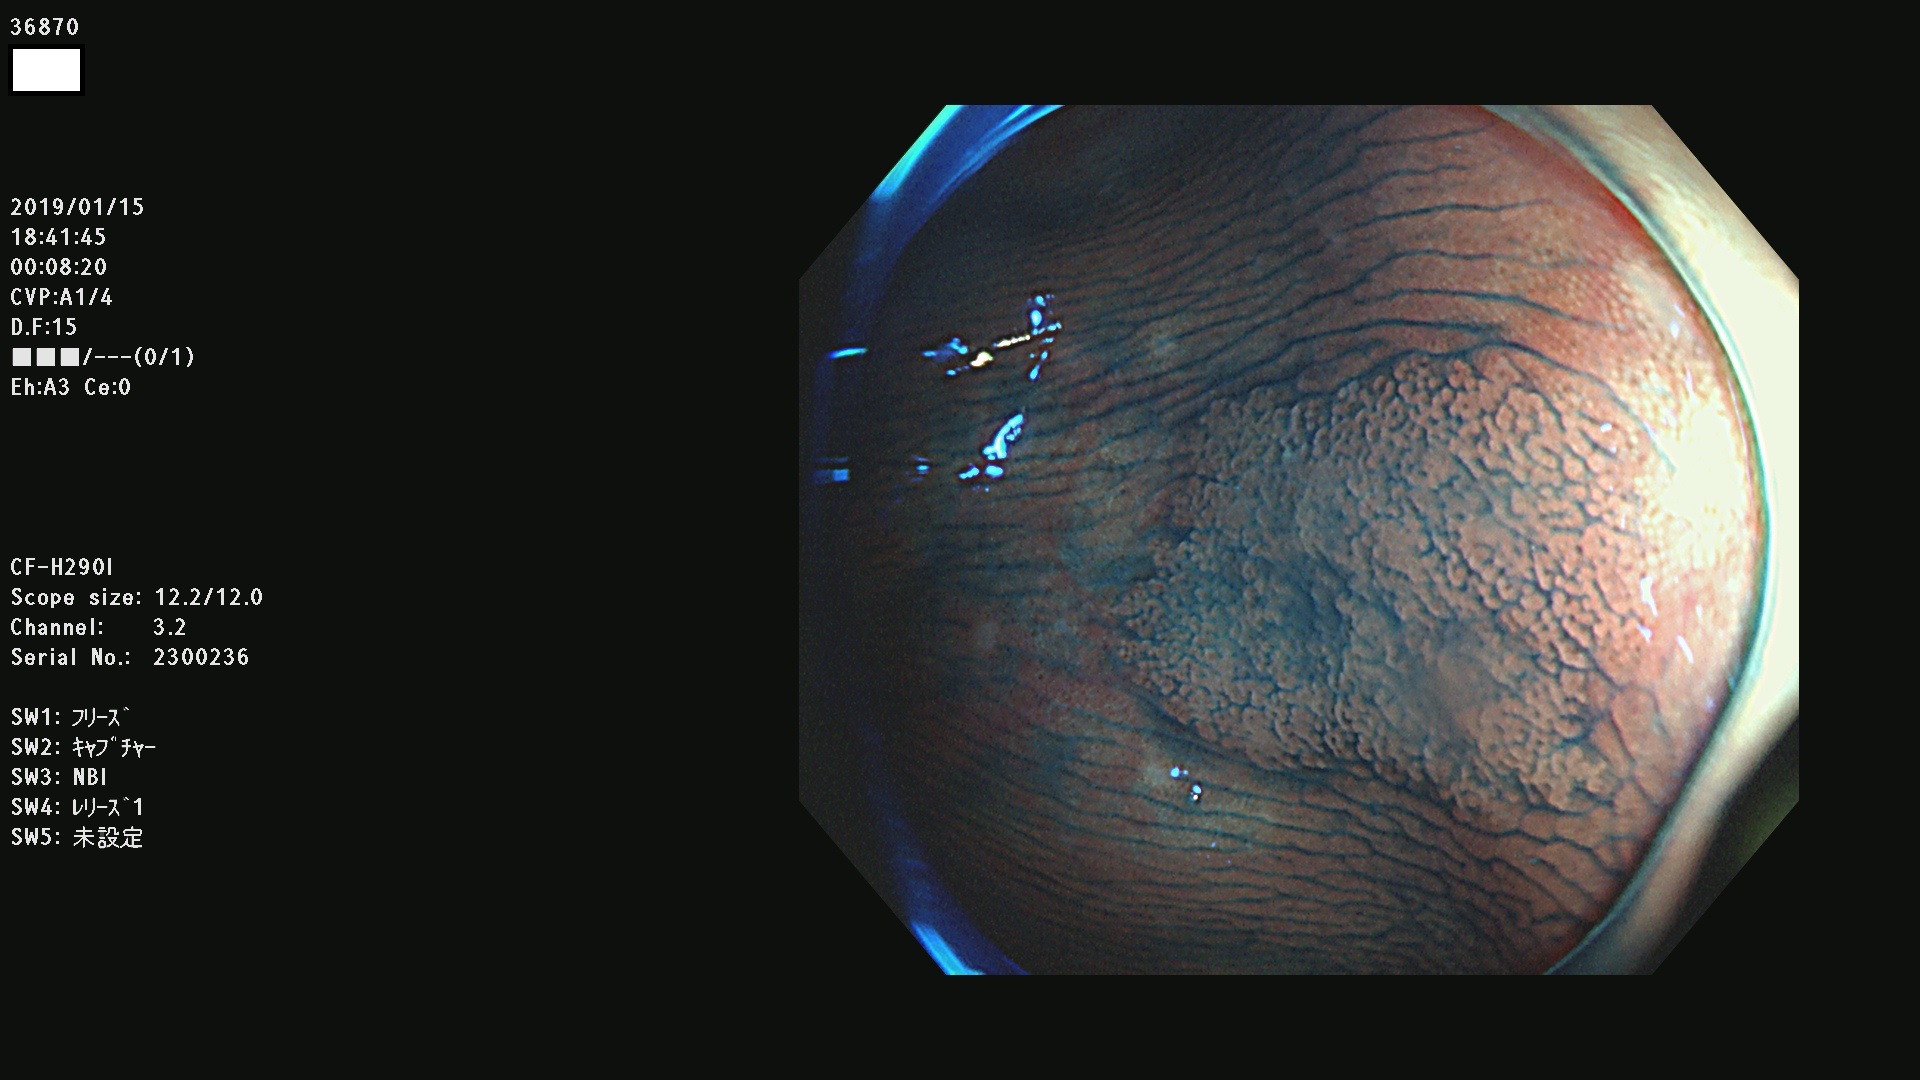

36804 36806 36807 36808 36809 36810 36811 36813 36815 36816 36817 36818 36820 36821 36822 36824 36825 36826 36828 36829 36830 36831 36832 36833 36834 36835 36837 36840 36841 36842 36845 36846 36848 36849 36851 36852 36853 36854 36855 36857 36859 36860 36861 36862(SSAPのみ) 36863 36864 36866 36868 36869 36870 36873 36875 36877 36878 36879 36881 36882 36883 36884 36885 36886 36887 36888 36889 36891 36892 36893 36894 36895 36896 36897 36898 36899

発見困難で危険性の高い平坦型病変(上記100名より抽出)